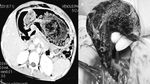

Dokter menemukan gumpalan bola rambut di lambung seorang pasien perempuan berusia 18 tahun. Ia sebelumnya sempat mengeluhkan keluhan nyeri perut dan muntah selama 15 hari. (Foto: F1000 Research)

Dokter menemukan biji jarak tersangkut di rongga hidung seorang bocah 7 tahun. Bocah itu awalnya mengalami mimisan satu hari sampai akhirnya dibawa ke rumah sakit. (Foto: F1000 Research)

Seorang wanita 17 tahun dilarikan ke UGD rumah sakit mengeluhkan nyeri hebat di perut bagian bawah. Setelah diperiksa dokter menemukan benda asing berupa kayu dililit kapas dari area intimnya. Rupanya pasien memiliki riwayat pernah mencoba aborsi di dukun desanya. (Foto: F1000 Research)

Perempuan 50 tahun pergi ke rumah sakit dengan keluhan nyeri leher dan kepala lebih dari satu tahun. Setelah dilakukan pemeriksaan mendalam, dokter menemukan sebuah benda asing di kepalanya. Terungkap, pasien pernah mengalami trauma 10 tahun lalu dan tidak mengetahui ada paku tertinggal dalam kepalanya. (Foto: F1000 Research)